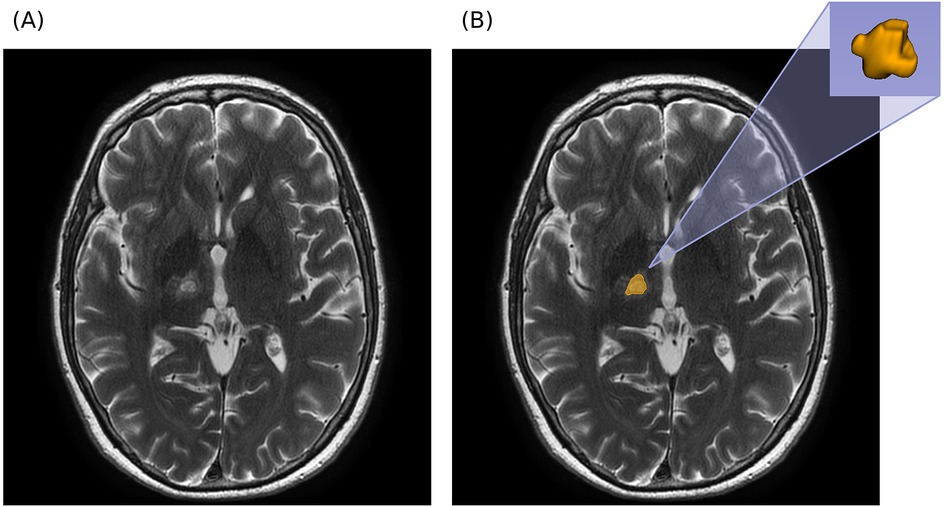

Objective: Magnetic resonance-guided focused ultrasound (MRgFUS) thalamotomy is an effective treatment for essential tremor (ET) and tremor-dominant Parkinson's disease (PD), yet a substantial proportion of patients experience tremor recurrence over time. Reliable imaging biomarkers to predict long-term outcomes are lacking. The purpose of the study was to evaluate whether radiomic features extracted from 24-hour post-treatment MRI can predict clinically relevant tremor recurrence at 12 months after MRgFUS thalamotomy, using a machine learning (ML) approach. Materials and Methods: Retrospective, single-center study included 120 patients (61 ET, 59 PD) treated with unilateral MRgFUS Vim thalamotomy between February 2018 and June 2023. Tremor severity was assessed using part A of the Fahn–Tolosa–Marin Tremor Rating Scale (FTM-TRS) at baseline and 12 months. Recurrence was defined as an FTM-TRS part A score ≥ 3 at 12 months. Lesions were manually segmented on 24-hour post-treatment T2-weighted MRI. Forty radiomic features (18 first-order, 22 texture GLCM from Laplacian of Gaussian–filtered images) were extracted. A linear Support Vector Classifier with leave-one-out cross-validation was used for classification. Model explainability was assessed using SHapley Additive exPlanations (SHAP). Results: Clinically relevant tremor recurrence occurred in 23 patients (19%). For the full cohort, the ML model achieved a balanced accuracy of 0.720, weighted F1-score of 0.737, and comparable sensitivity and specificity across classes. Performance was higher in PD (BA = 0.808, F1 = 0.793) than in ET (BA = 0.580, F1 = 0.696). The most predictive features were texture-derived GLCM metrics, particularly from edge-enhanced images, with first-order features contributing complementary information. No significant correlations were found between radiomic features and procedural parameters. Conclusion: Radiomic analysis of MRgFUS lesions on 24-hour post-treatment MRI can provide early prediction of 12-month tremor recurrence, with higher predictive value in PD than in ET. Texture-based features may capture microstructural characteristics linked to treatment durability. This approach could inform post-treatment monitoring and individualized management strategies.